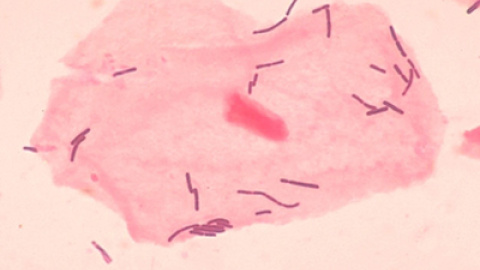

En unas muestras de calostro, el líquido que secretan las mamas los días que suceden al parto, han encontrado más de 700 especies de estos microorganismos, más de los que inicialmente esperaban los expertos. Los resultados se publican en el American Journal of Clinical Nutrition.

Los géneros bacterianos más presentes en las muestras de calostro se corresponden con las bacterias Weissella, Leuconostoc, Staphylococcus, Streptococcus y Lactococcus, mientras que en las correspondientes al fluido que se desarrolla entre el primer y el sexto mes de lactancia se observó la aparición de bacterias típicas de la cavidad bucal como Veillonella, Leptotrichia y Prevotella. "Todavía no se ha podido determinar si estas bacterias colonizan la boca del bebé o si las bacterias de la boca del lactante entran en la leche materna cambiando su composición", apuntan los autores.